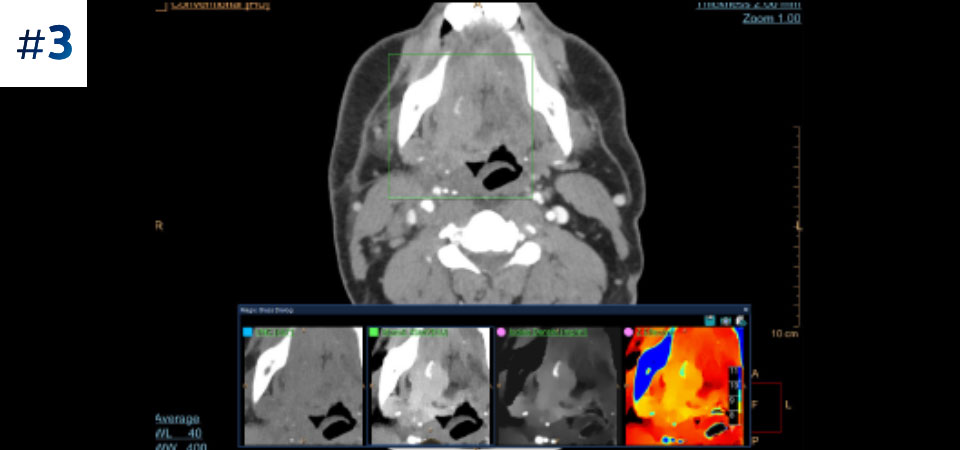

Vá além da CT convencional. Veja de que forma os vários tipos de resultados obtidos com deteção espectral podem aumentar a fiabilidade do seu diagnóstico.

Massa do pescoço

Conheça a diferença entre a CT com detetor espectral e a CT convencional